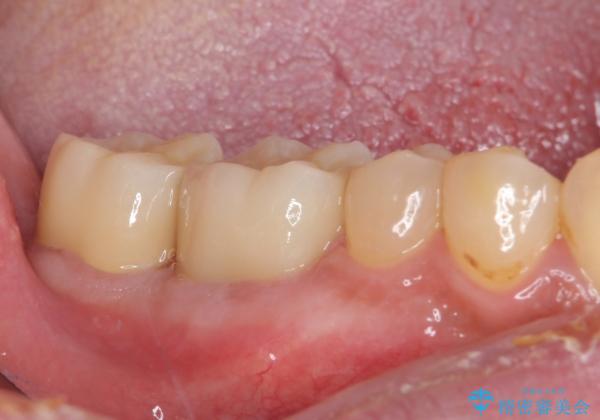

外科処置後の経過を待って、フルジルコニアクラウンにて補綴することとしました。

通っていた歯科医院では、抜歯の可能性が高いと言われていたようですが、何とか健全な状態で歯を保存することができました。